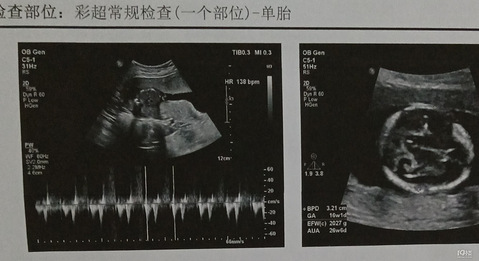

预产期:2024.3.25 建卡医院:镇卫生院 产检医院:早期在卫生院,中后期在恩泽 宝宝小名:没想好 生产医院:准备去路桥恩泽 B超照片: